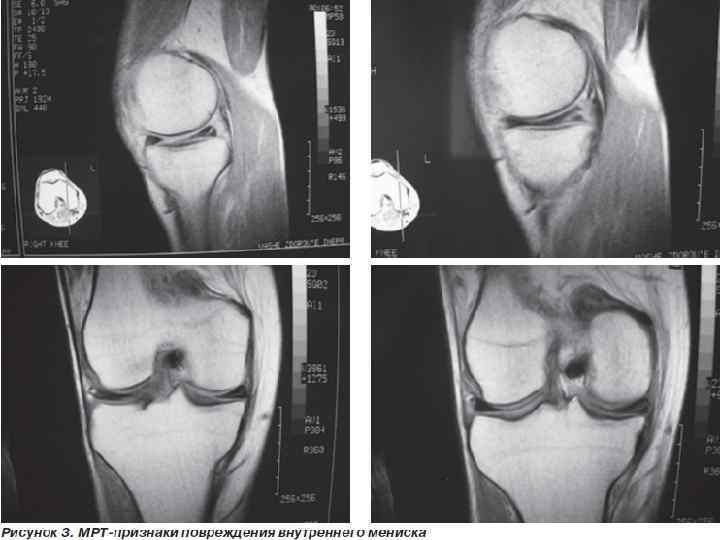

Виды повреждений. Отрыв мениска от мест прикрепления в области заднего и переднего рогов и тела мениска в паракапсулярной зоне; Разрывы заднего и переднего рогов и тела мениска в трансхондральной зоне; Различные комбинации перечисленных повреждений; Чрезмерная подвижность менисков (разрыв межменисковых связок, дегенерация мениска); Хроническая травматизация и дегенерация менисков (менископатия посттравматического и статического характера — варусное или вальгусное колено; Кистозное перерождение менисков (наружного).

Виды повреждений. Разрывы менисков могут быть полными, неполными, продольными ( «ручка лейки» ), поперечными, лоскутообразными, раздробленными. Чаще повреждается тело мениска с переходом повреждения на задний или передний рог ( «ручка лейки» ). Изолированное повреждение заднего рога, переднего рога; Разрывы со смещением оторванной части и без смещения; Разрывы медиального мениска с повреждением бокового капсульно-связочного аппарата; при повторных блокадах со смещением оторванной части мениска травмируются передняя крестообразная связка и хрящ внутреннего мыщелка бедра (хондромаляция ).